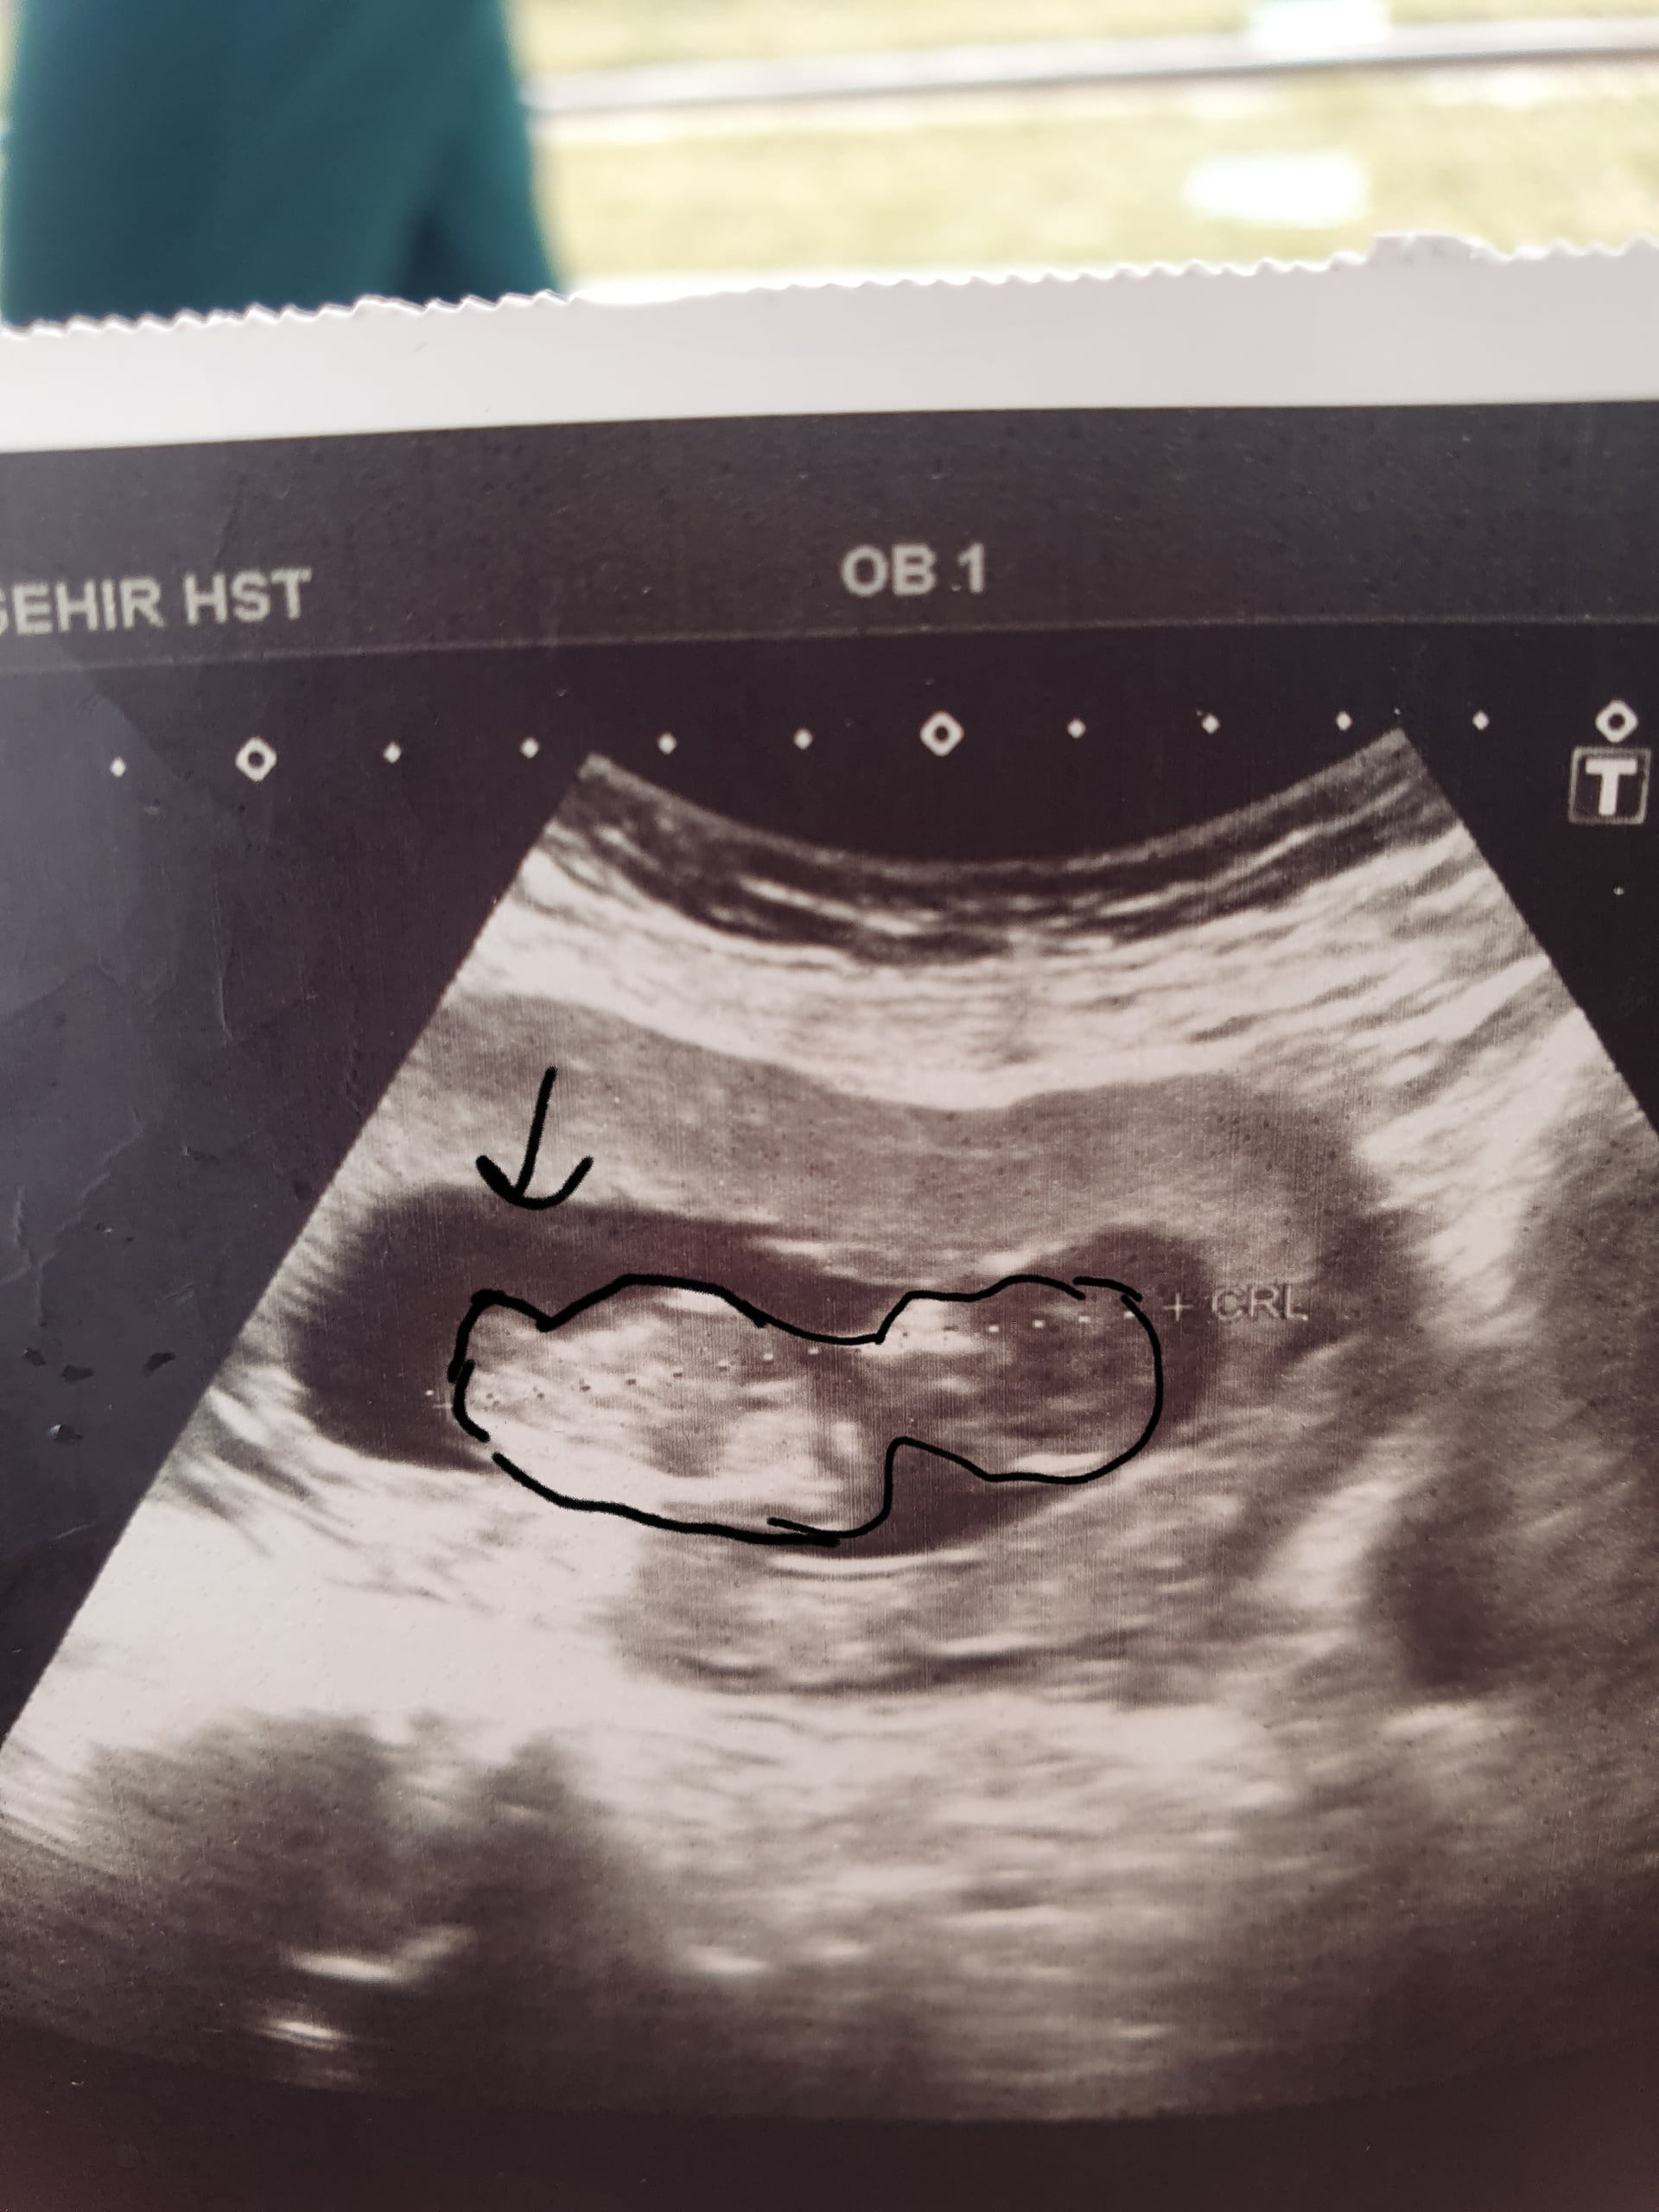

Tabi ultrason fotona bakabilir miyim :blush:

Yaaa doktorda bacagi kpali ama cikinti yok dedi nasip gonlumden erkek geciodu Rabbim hayirlisini versin

Boyle bulunuomus aslinda

Bende cizdim erkek gibi geldi ustte cikinti nub olabilir die ama baska biryerde net kiz bu diyenler olmus doktorda kiza benzetti gbi

Boyle cizdim ben aslinda ozele gitsem hemen ogrenirim de 3 hafta bekleyim diorum